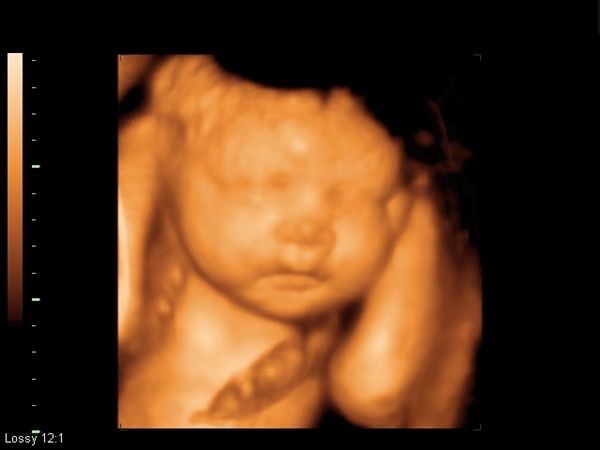

Ultrasonido 3D y 4D.